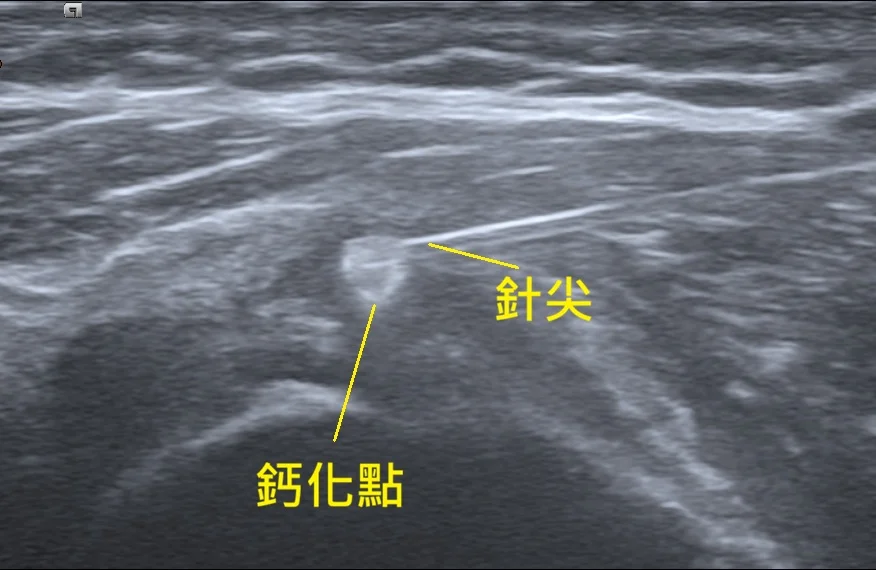

打了幾十次震波都沒用?50歲大姐的肩膀「頑石」消除記—超音波導引鈣化沖洗術

一位飽受肩膀劇痛折磨的50歲女性,歷經數月、數十次震波治療無效,生活幾近停擺。來到宸新後,透過高階超音波揪出導致疼痛的「頑固鈣化結石」。在嘗試高能量震波仍未改善後,醫師果斷採取「超音波導引鈣化沖洗術」,直接將肌腱內的結石「洗」出來,兩週後重獲新生。